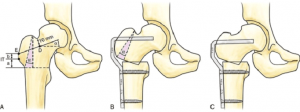

هدف مداخلات پزشکی بازگرداندن زاویه بین گردن و تنه فمور و realignment صفحه آپوفیزی است تا میزان نیروهای برشی کاهش پیدا کند و استخوان سازی در گردن فمور در جهت ایجاد ترابکولاهای نرمال انجام شود.

درمان جراحی

اولین قدم در درمان این اختلال جراحی نیست زیرا زاویه بین گردن و تنه فمور در دوران کودکی تغییرات زیادی پیدا می کند در صورتی که اختلال شدید شود و منجر به کوتاهی اندام و بی حرکتی شود درمان جراحی ( Varus osteotomy) لازم است که در ناحیه تروکانتریک و ساب تروکانتریک انجام می شود.

در صورتی که کوکسا والگا با آنته ورژن همراه باشد درمان های جراحی (rotational ) این اختلال همراه باید مد نظر باشد.